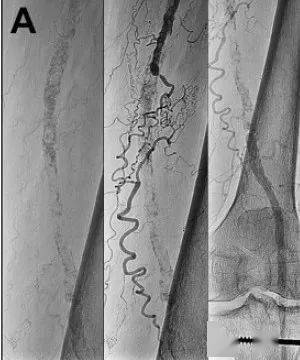

腘动脉瘤介入腔内隔绝 (重医附一院 术者:代远斌 贺俊文 张红光)

图片尺寸1200x1600